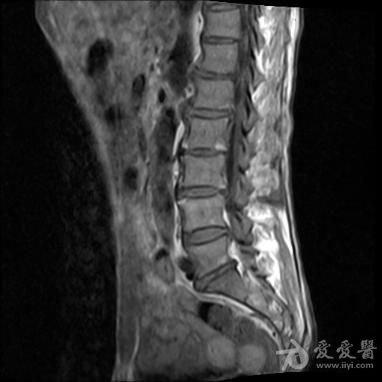

4、出现了腰部问题

男性患有腰椎间盘突出、腰肌劳损以及椎间盘位置不正等,在性生活的时候都会出现拉牵性的疼痛感。当腰部神经的脏器发生病变时也会导致腰痛。